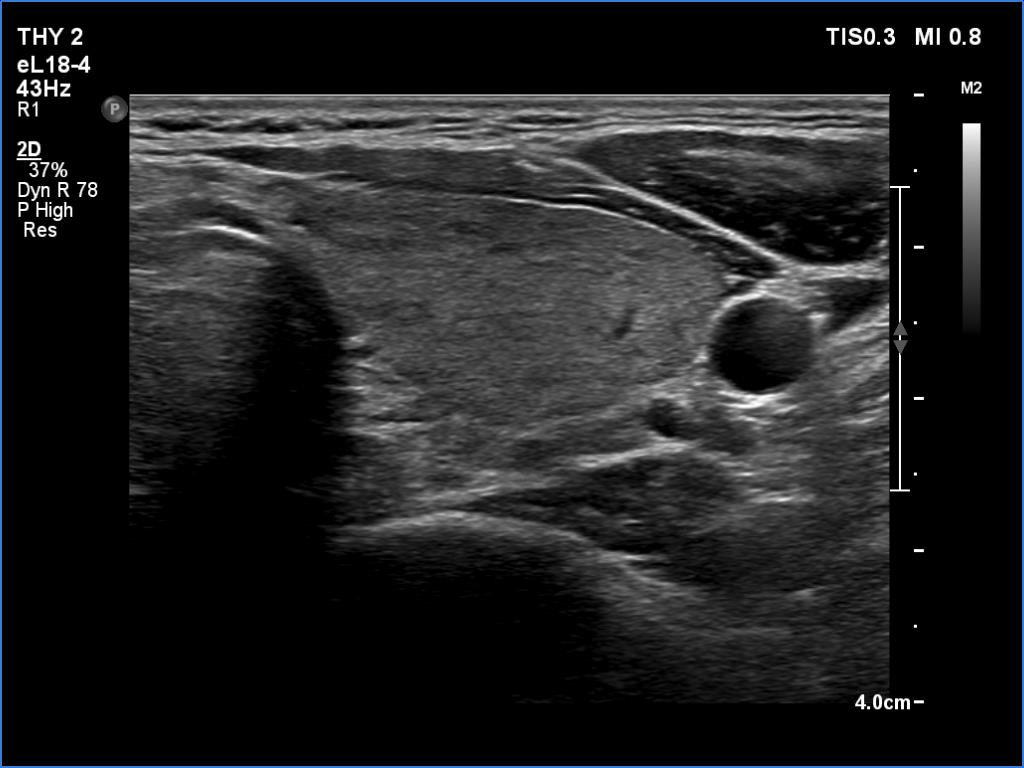

Right lobe, transverse scan

Left lobe, transverse scan